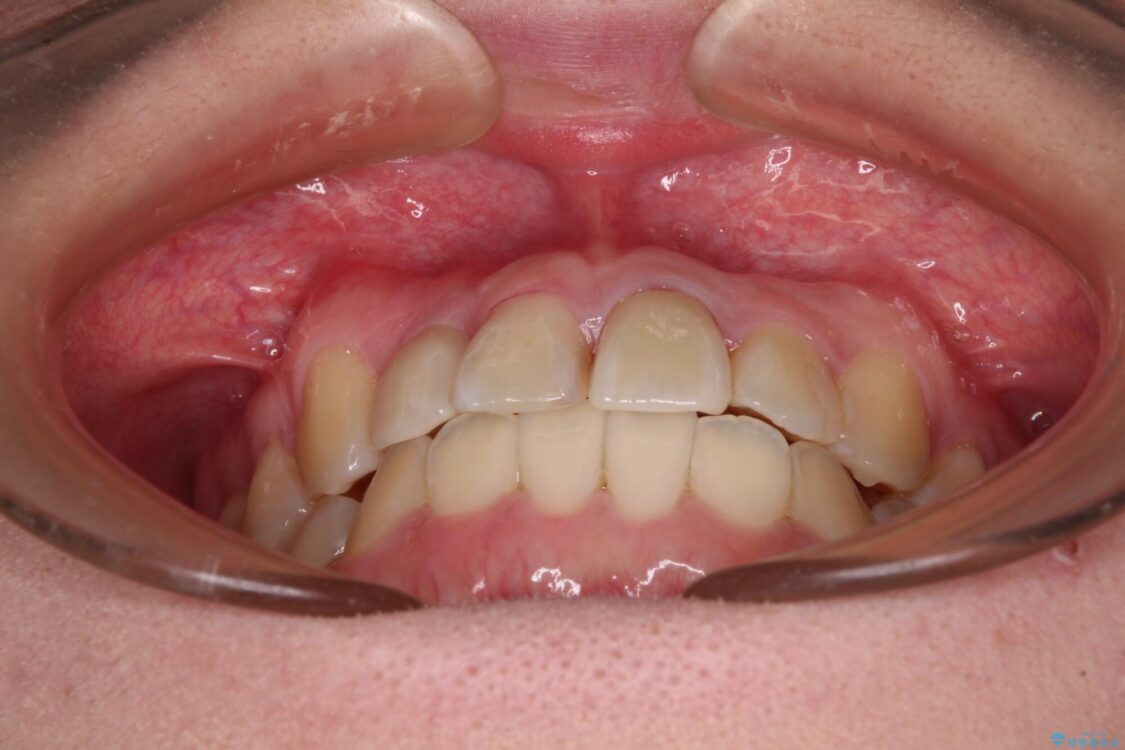

治療前

• 虫歯治療ついでに歯並びの後戻りを改善 インビザラインによる矯正治療 治療前画像